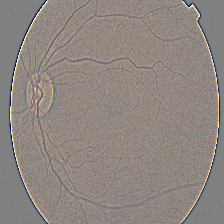

What it does: AI Cura utilizes artificial intelligence to predict diabetic retinopathy and kidney diseases in diabetic patients, offering accurate and timely diagnostic capabilities. By analyzing medical imaging data and biomarkers, AI Cura enables proactive interventions and personalized treatment plans, revolutionizing diabetic care.

How we built it: Research Paper Used- https://www.aao.org/eye-health/diseases/what-is-diabetic-retinopathy The development of AI Cura involved leveraging deep learning algorithms and advanced image processing techniques. We curated extensive datasets comprising diverse medical images and patient profiles, trained AI models to recognize disease patterns, and rigorously validated their performance across different patient cohorts and imaging modalities.